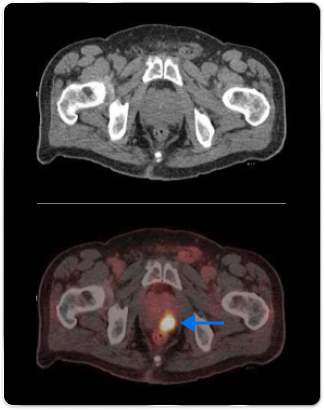

High-risk patient with newly diagnosed prostate cancer

Age

63

PSA (ng/mL)

26

Gleason Score

4 + 3

PYLARIFY may have helped prevent overtreatment